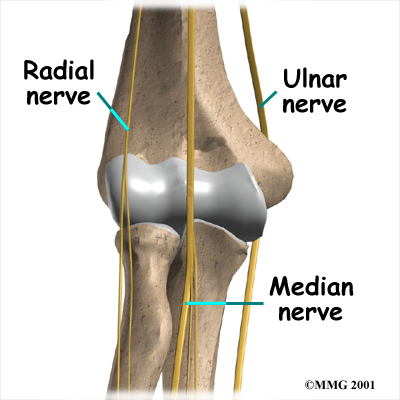

Nerves

All of the nerves that travel down the arm pass across the elbow. Three main nerves that innervate the arm, forearm, and hand begin together at the shoulder: the radial nerve, the ulnar nerve, and the median nerve. These nerves carry signals from the brain to the muscles that move the arm. The nerves also carry signals back to the brain about sensations such as touch, pain, and temperature.

Some of the more common problems around the elbow are problems of the nerves. Each nerve travels through its own tunnel as it crosses the elbow. Due to the elbow having to bend a lot, the nerves must bend as well. Constant bending and straightening can lead to irritation or pressure on the nerves within their tunnels and cause problems such as pain, numbness, and weakness in the arm and hand.